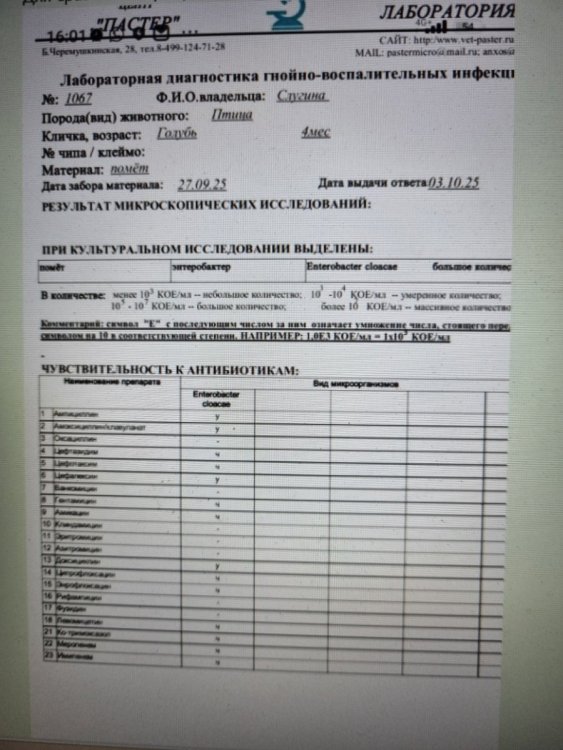

Это не у меня только так, вот люди в соседней теме сдавали параллельно в двух лабораториях, в одной лаборатории есть чувствительность к доксициклину, в другой нет